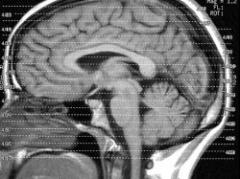

Descubrimientos han aseverado que el ejercicio fÃsico ayuda a preservar la memoria y que aumenta el volumen de las zonas cerebrales relacionadas con esa función cognitiva.ver más

Una nueva investigación descubrió que los expertos en juegos de mesa, como el ajedrez, utilizan una región del cerebro que el resto no solemos usar.ver más

Un estudio llevado a cabo en la Universidad de Basilea, Suiza, demostró que es más efectivo recordar mientras dormimos que hacerlo mientras estamos despiertos.ver más